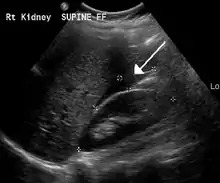

Blood in Morrison's pouch between the liver and kidney due to a ruptured ectopic pregnancy

The most common complication is rupture with internal bleeding which may lead to hypovolemic shock. Damage to the fallopian tubes can lead to difficulty becoming pregnant in the future. The woman's other fallopian tube may function sufficiently for pregnancy. After the removal of one damaged fallopian tube, pregnancy remains possible in the future. If both are removed, in-vitro fertilization remains an option for women hoping to become pregnant.[10][11][12]

A small amount of anechogenic-free fluid in the recto-uterine pouch is commonly found in both intrauterine and ectopic pregnancies.[5] The presence of echogenic fluid is estimated at between 28 and 56% of women with an ectopic pregnancy, and strongly indicates the presence of hemoperitoneum.[5] However, it does not necessarily result from tubal rupture but is commonly a result from leakage from the distal tubal opening.[5] As a rule of thumb, the finding of free fluid is significant if it reaches the fundus or is present in the vesico-uterine pouch.[5] A further marker of serious intra-abdominal bleeding is the presence of fluid in the hepatorenal recess of the subhepatic space.[5]